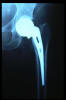

Fractura cuello fémur. Prótesis completa.